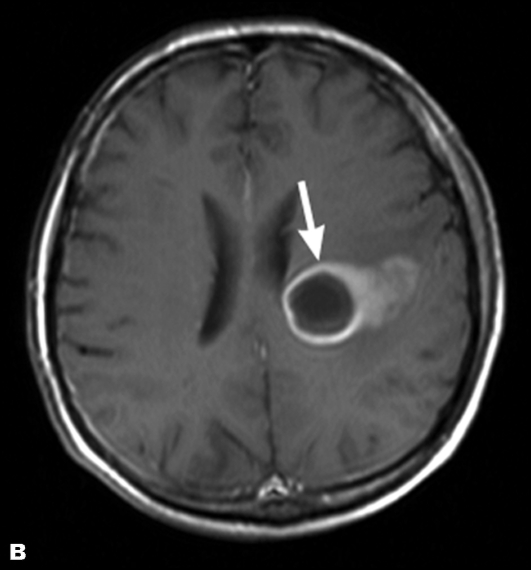

Абсцесс мозга

Абсцесс мозга – это, пожалуй, самая запущенная и опасная стадия. Причиной развития заболевания является излишнее накопление гноя. На начале своего зарождения абсцесс практически ничем не отличается от острого отита, развивается наряду с ним и не обладает сильно выраженной симптоматикой, поэтому выявить этот недуг с первого раза почти невозможно. Для перехода из начальной стадии в более явную, заболеванию требуется около 14 дней, поэтому пациент, вовремя не обратившийся за помощью к специалисту, может вовсе не подозревать о наличии у него абсцесса мозга.

Очень редко заболевание провоцирует шум в ушах, однако такой симптом при абсцессе может стать следствием образования опухоли мозга. В любом случае, пациент должен незамедлительно обратиться к врачу, так как самолечение здесь совсем неуместно, и может только навредить.